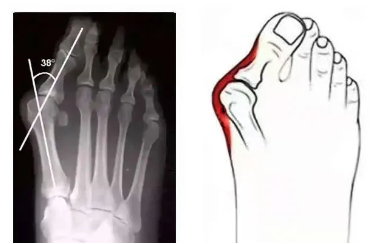

踇外翻,俗称“大脚骨”,是一种常见的足部畸形。它不仅影响足部的美观,更会给我们的生活带来诸多不便。据统计,踇外翻的发病人群中,女性与男性的比例约为 30:1,且多呈对称性。其主要表现为足趾斜向外侧,第一骨内翻,第一二骨间夹角增大,趾关节轻度半脱位,第一骨头上形成骨赘,长期受鞋帮摩擦后,局部皮肤增厚,严重时还会红肿发炎,形成令人烦恼的囊炎。

然而,当踇外翻发展到较为严重的程度,保守治疗效果不佳时,手术治疗就成为必要的选择。手术的目的是纠正趾的畸形,恢复足部的正常结构和功能。目前有多种手术方法可供选择,如截骨术、软组织手术等。截骨术主要是针对骨骼结构的改变,通过对第一骨等相关骨骼进行切割、重新定位和固定,来调整趾的力线。而软组织手术则侧重于对趾周围的韧带、肌肉等软组织进行修复和调整。手术治疗需要根据患者的具体情况,如年龄、健康状况、踇外翻的严重程度等因素进行综合评估,选择较为适合的手术方案。